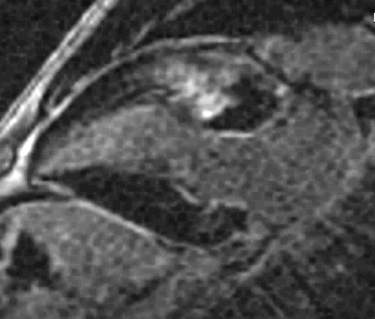

Fig.1., 2.: Hypertrophic obstructive cardiomyopathy: Longitudinal and short axis slices of delayed enhancement of contrast material in the heart: pathologic enhancement is visible in the myocardium in the asymmetrically thickened left ventricular wall, referring to a degenerative-fibrotic process.

Fig.: 6., 7., 8.: MRI: Extended myocardial infarct of the inferior ventricular wall Late phase contrast enhancement in the thin inferior wall of the ventricle in cross sectional and longitudinal images, MRI